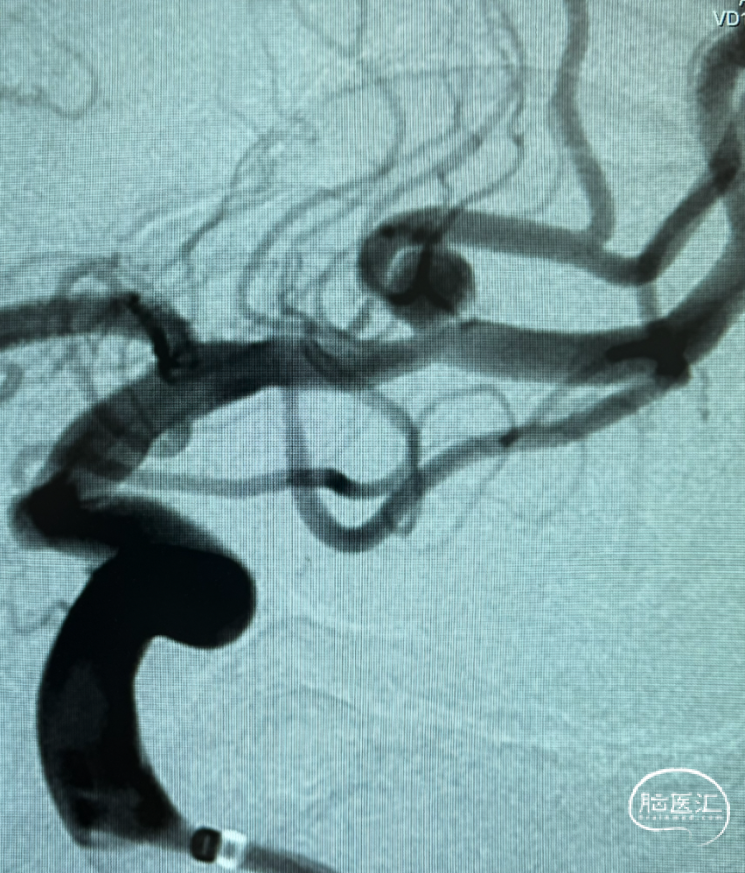

术前影像检查

三维旋转图像:左侧大脑中动脉早额支起始部囊性动脉瘤。

动脉瘤参数:最大径4.4mm,瘤高3.5mm,瘤颈宽3.5mm,载瘤动脉直径1.3mm。

工作角度造影。